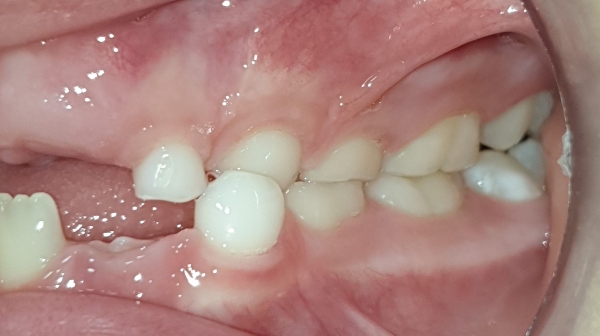

DESPUÉS